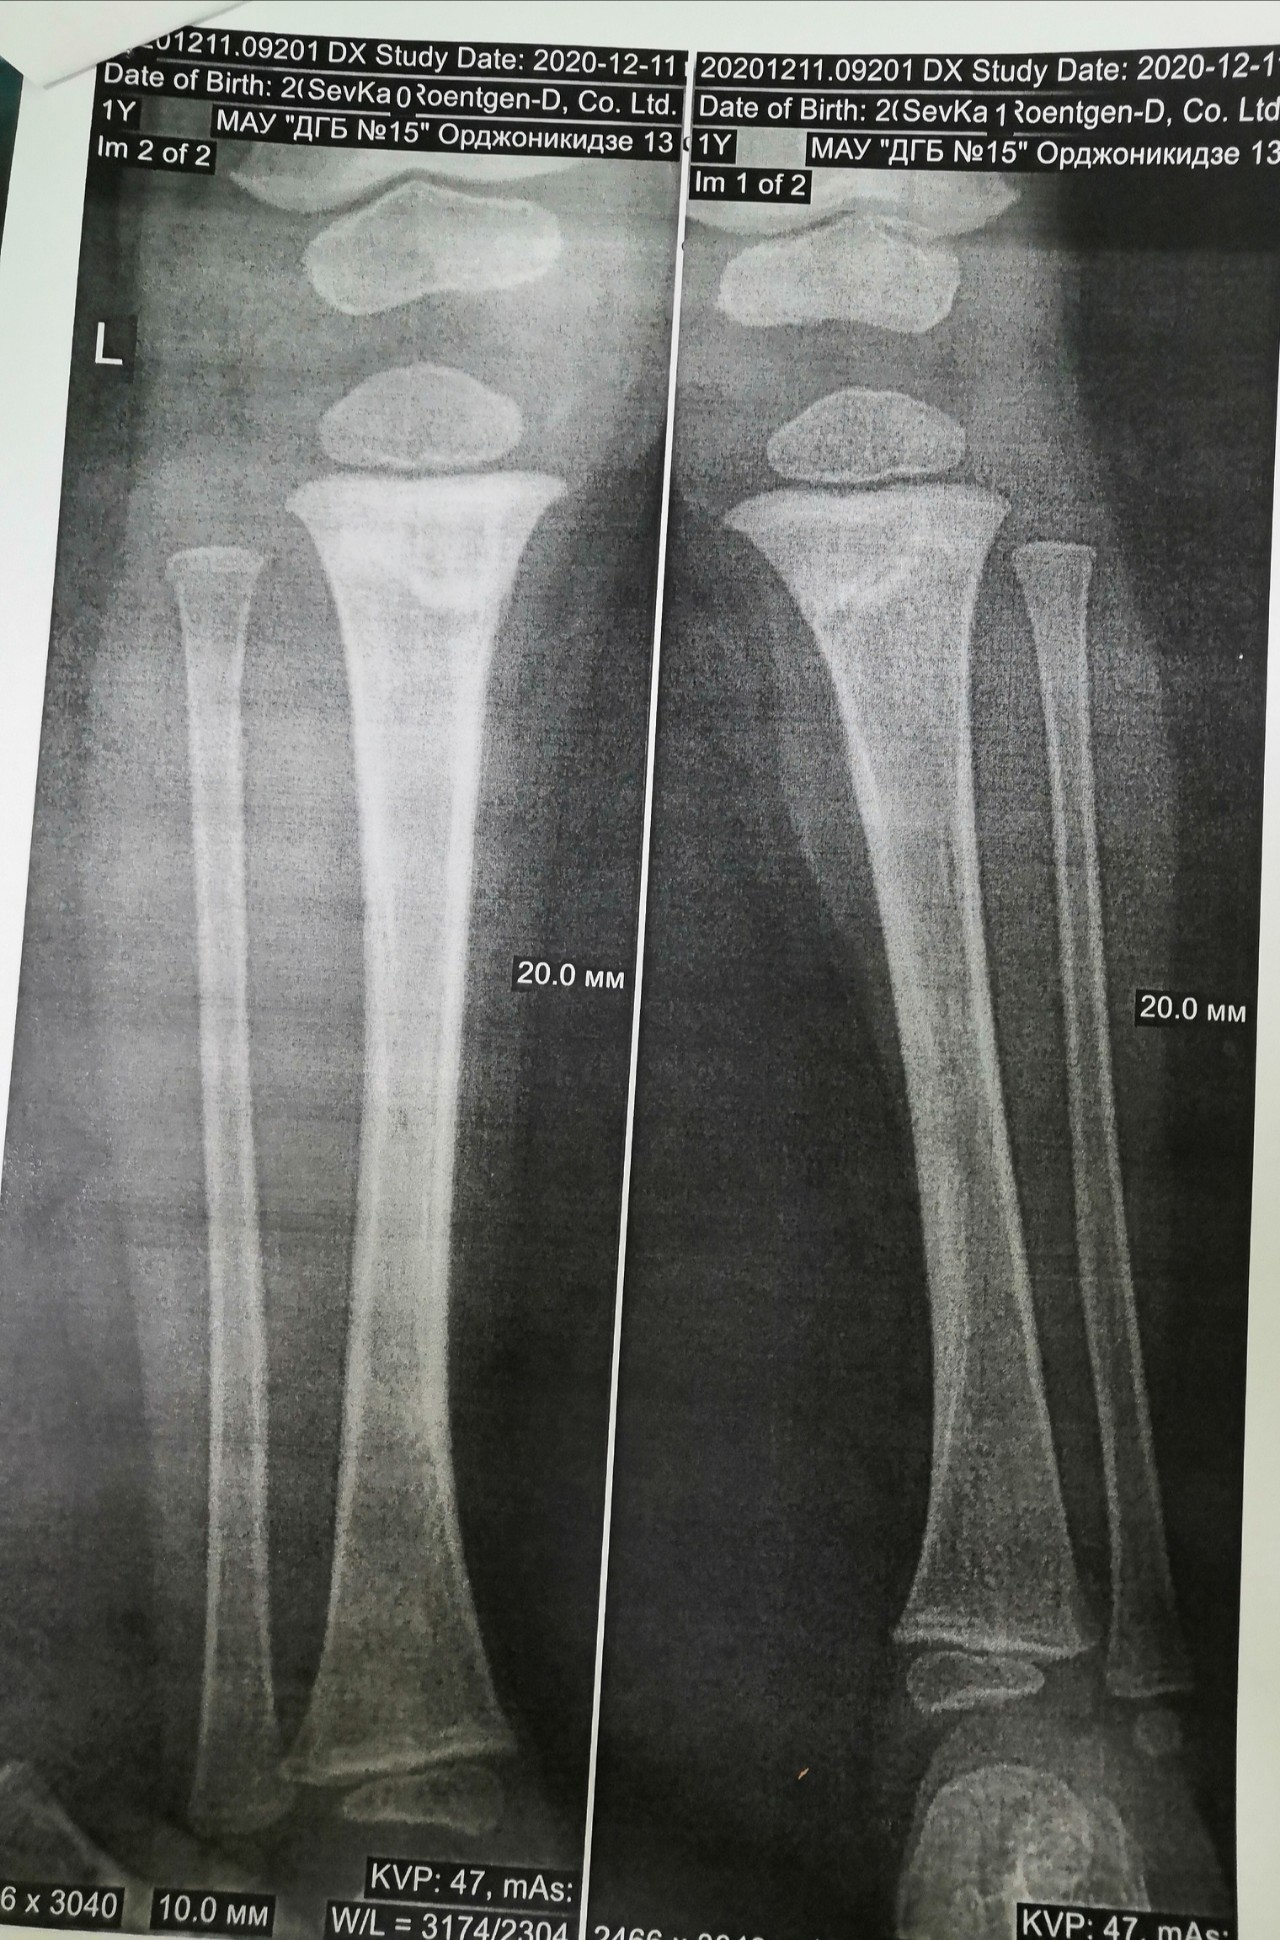

Перелом большой берцовой кости - серьезное повреждение, сопровождающееся болезненными ощущениями и нарушением функции ноги. На этой странице вы найдете много фотографий, позволяющих вам более детально изучить эту травму.

Большеберцовая кость рентген

Здесь представлены медицинские изображения переломов большой берцовой кости, сделанные врачами в процессе диагностики и лечения. Вы сможете увидеть, как выглядит этот тип травмы на рентгеновских снимках и других медицинских изображениях.